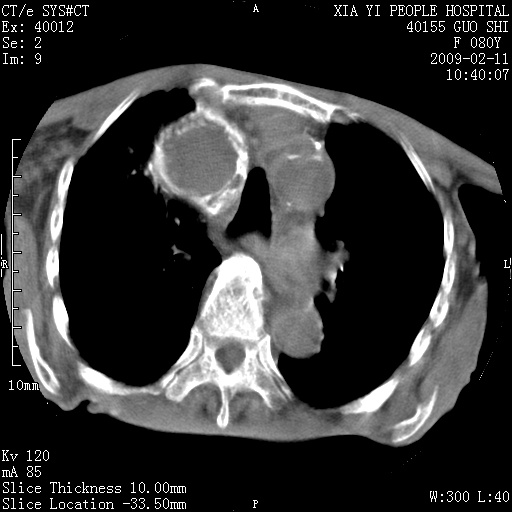

以下是引用随光逐影在2009-2-16 16:34:00的发言:[br]1)考虑右前纵隔皮样囊肿。2)双侧少量胸腔积液。

以下是引用zjzjr在2009-2-16 17:30:00的发言:[br]支持囊性畸胎瘤 双侧少量胸腔积液。